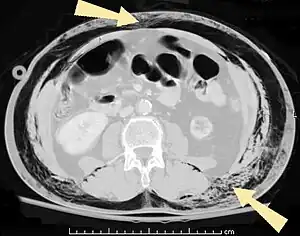

Pneumoperitoneum (or peritoneal emphysema) is air or gas in the abdominal cavity, and is most commonly caused by gastrointestinal perforation, often the result of surgery.

- Pneumoperitoneum (or peritoneal emphysema), air or gas in the abdominal cavity. The most common cause is a perforated abdominal viscus, generally a perforated peptic ulcer, although any part of the bowel may perforate from a benign ulcer, tumor or abdominal trauma.

- Pneumatosis intestinalis, air or gas cysts in the bowel wall